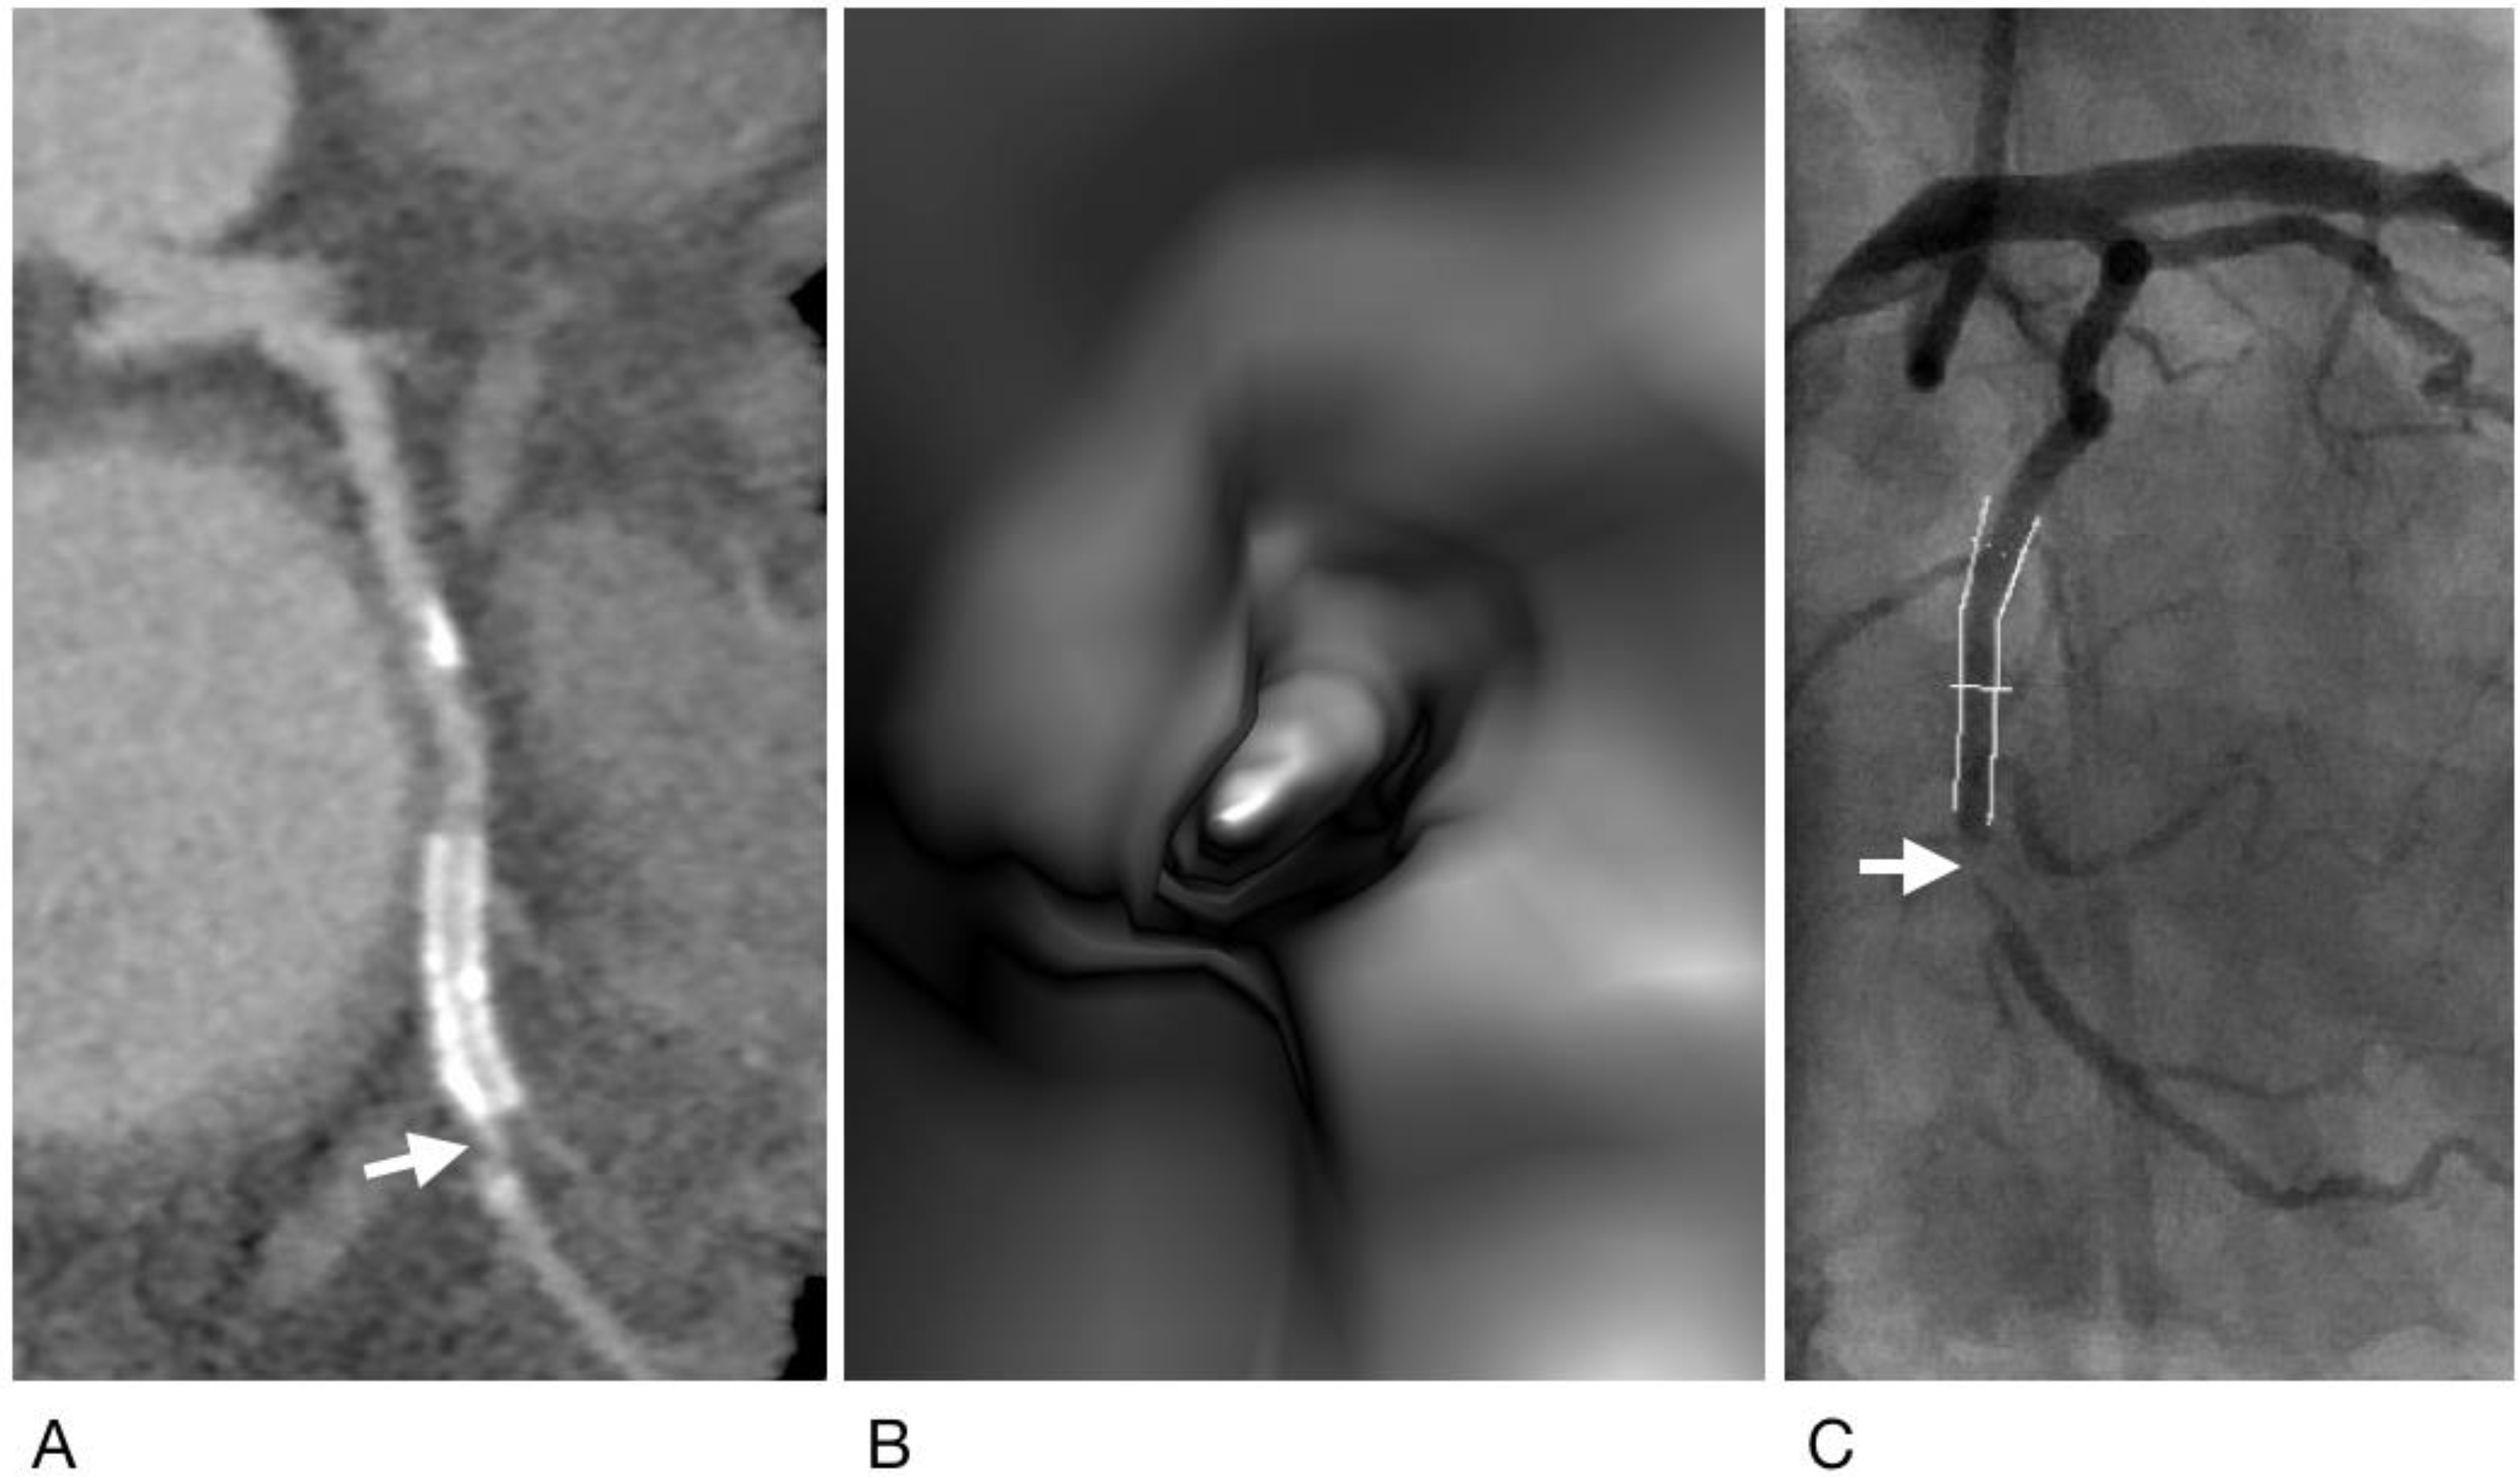

- Wan, Y.L.; Tsay, P.K.; Chen, C.C.; Juan, Y.H.; Huang, Y.C.; Chan, W.H.; Wen, M.S.; Hsieh, I.C. Coronary in-stent restenosis: Predisposing clinical and stent-related factors, diagnostic performance and analyses of inaccuracies in 320-row computed tomography angiography. Int. J. Cardiovasc. Imaging 2016, 32 (Suppl. 1), 105–115. [Google Scholar] [CrossRef]

- Sun, Z.; Winder, R.J.; Kelly, B.E.; Ellis, P.K.; Kennedy, P.T.; Hirst, D.G. Diagnostic value of CT virtual intravascular endoscopy in aortic stent-grafting. J. Endovasc. Ther. 2004, 11, 13–25. [Google Scholar] [CrossRef]

- Juan, Y.H.; Huang, Y.C.; Sun, Z.; Hsieh, I.C.; Chan, W.H.; Chen, C.C.; Hung, K.C.; Wen, M.S.; Wan, Y.L. The evolution and investigation of native coronary arteries in patients after coronary stent implantation: A study by 320-detector CT angiography. Int. J. Cardiovasc. Imaging 2014, 30 (Suppl. 1), 13–24. [Google Scholar] [CrossRef]